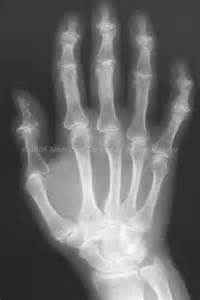

Radiographic signs: - Heberden’s nodes (DIP) - Decreased joint space with sclerosis - Asymmetrical distribution - Non-uniform loss of joint space

DJD in Hand